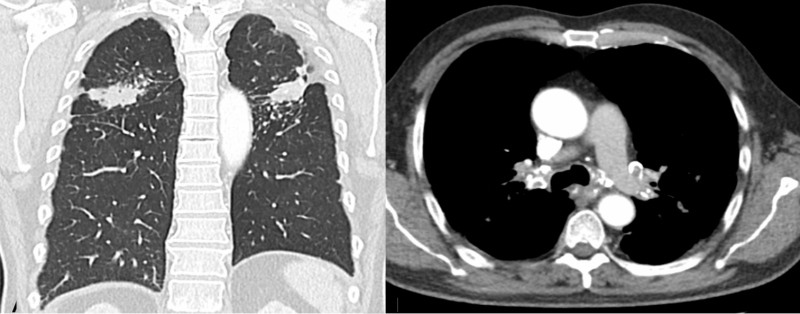

El paciente fue sometido a radioterapia de consolidación al tumor primario, seguido por tratamiento quirúrgico. Se realizó CT de tórax de control al año y medio del diagnóstico inicial, continuando sin cambios los hallazgos pulmonares. Se efectuó seguimiento periódico con antígeno carcinoembrionario (ACE) y marcador tumoral CA 19-9, que han sido negativos hasta la actualidad.